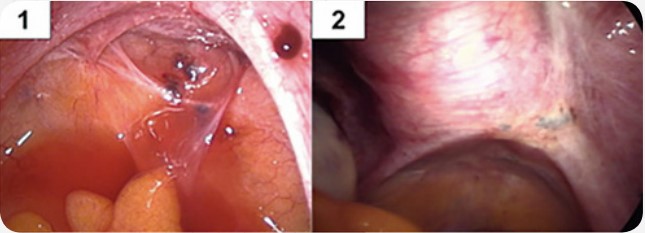

São lesões espalhadas na superfície do interior do abdômen. Podem estar disseminadas atingindo até mesmo o diafragma. Embora sejam superficiais, muitas vezes estão localizadas sobre órgãos nobres como no intestino, bexiga e ureter e, por isto os cuidados cirúrgicos devem ser bem observados para que se evitem complicações. Os sintomas mais comuns são: cólica, menstruação irregular e infertilidade. O exame clínico não apresenta alterações importantes, o ultrassom não demonstra imagens características e os marcadores que podem sugerir a presença da doença, dosados no sangue (CA125 e SAA) podem ou não estar alterados. O diagnóstico conclusivo e o tratamento são feitos pela videolaparoscopia.

1: lesão vermelha; 2 e 4: lesões negras; 3: lesão branca